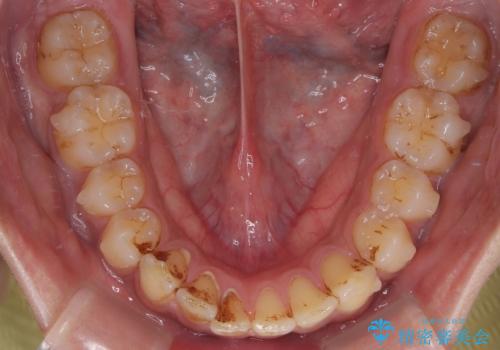

- 上の前歯の正中離開(すきっ歯)と、下顎前歯部の叢生(デコボコ)を主訴に来院された患者様の症例です。

「目立ちにくい装置で治療したい」とのご希望があり、透明のマウスピース矯正であるインビザラインを用いて矯正治療を行いました。